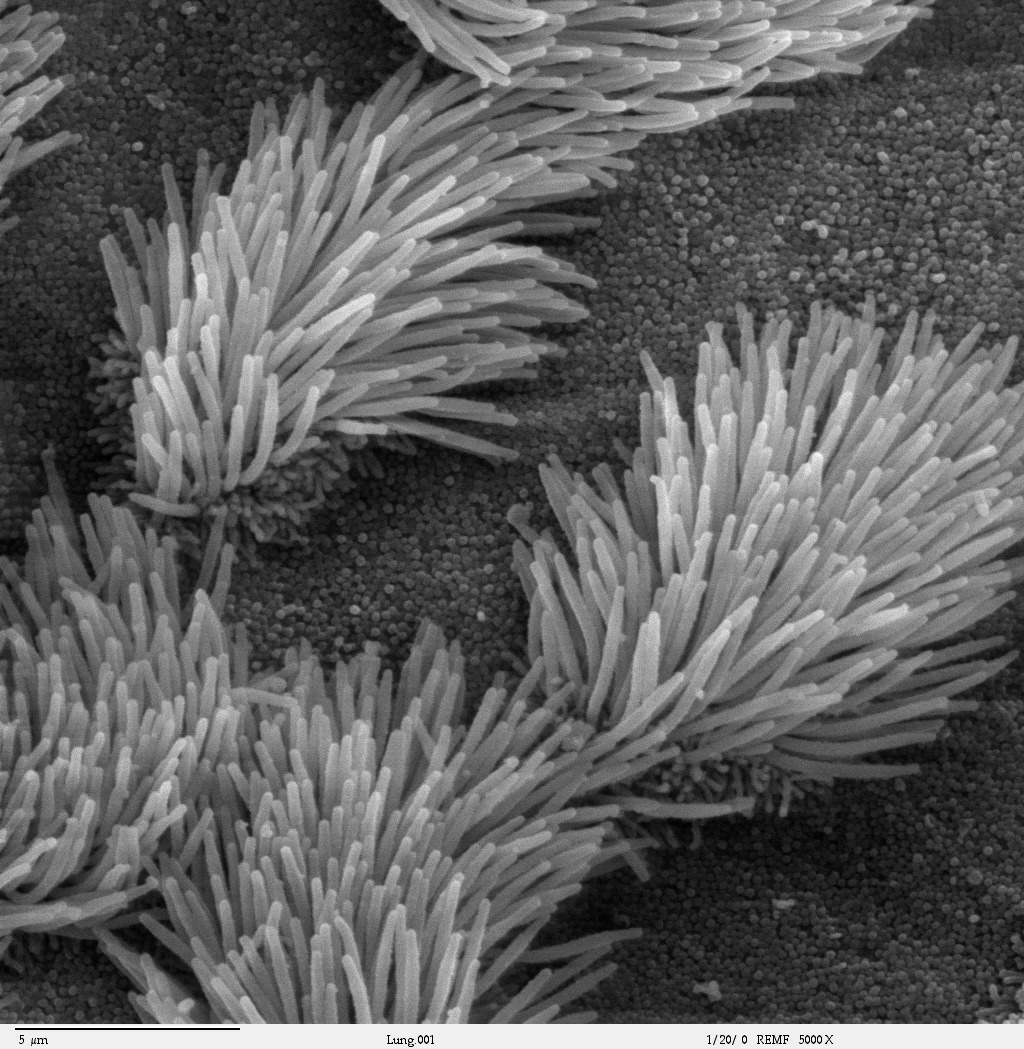

An almost identical lung cilia evidence for comparison. Smokefunction |